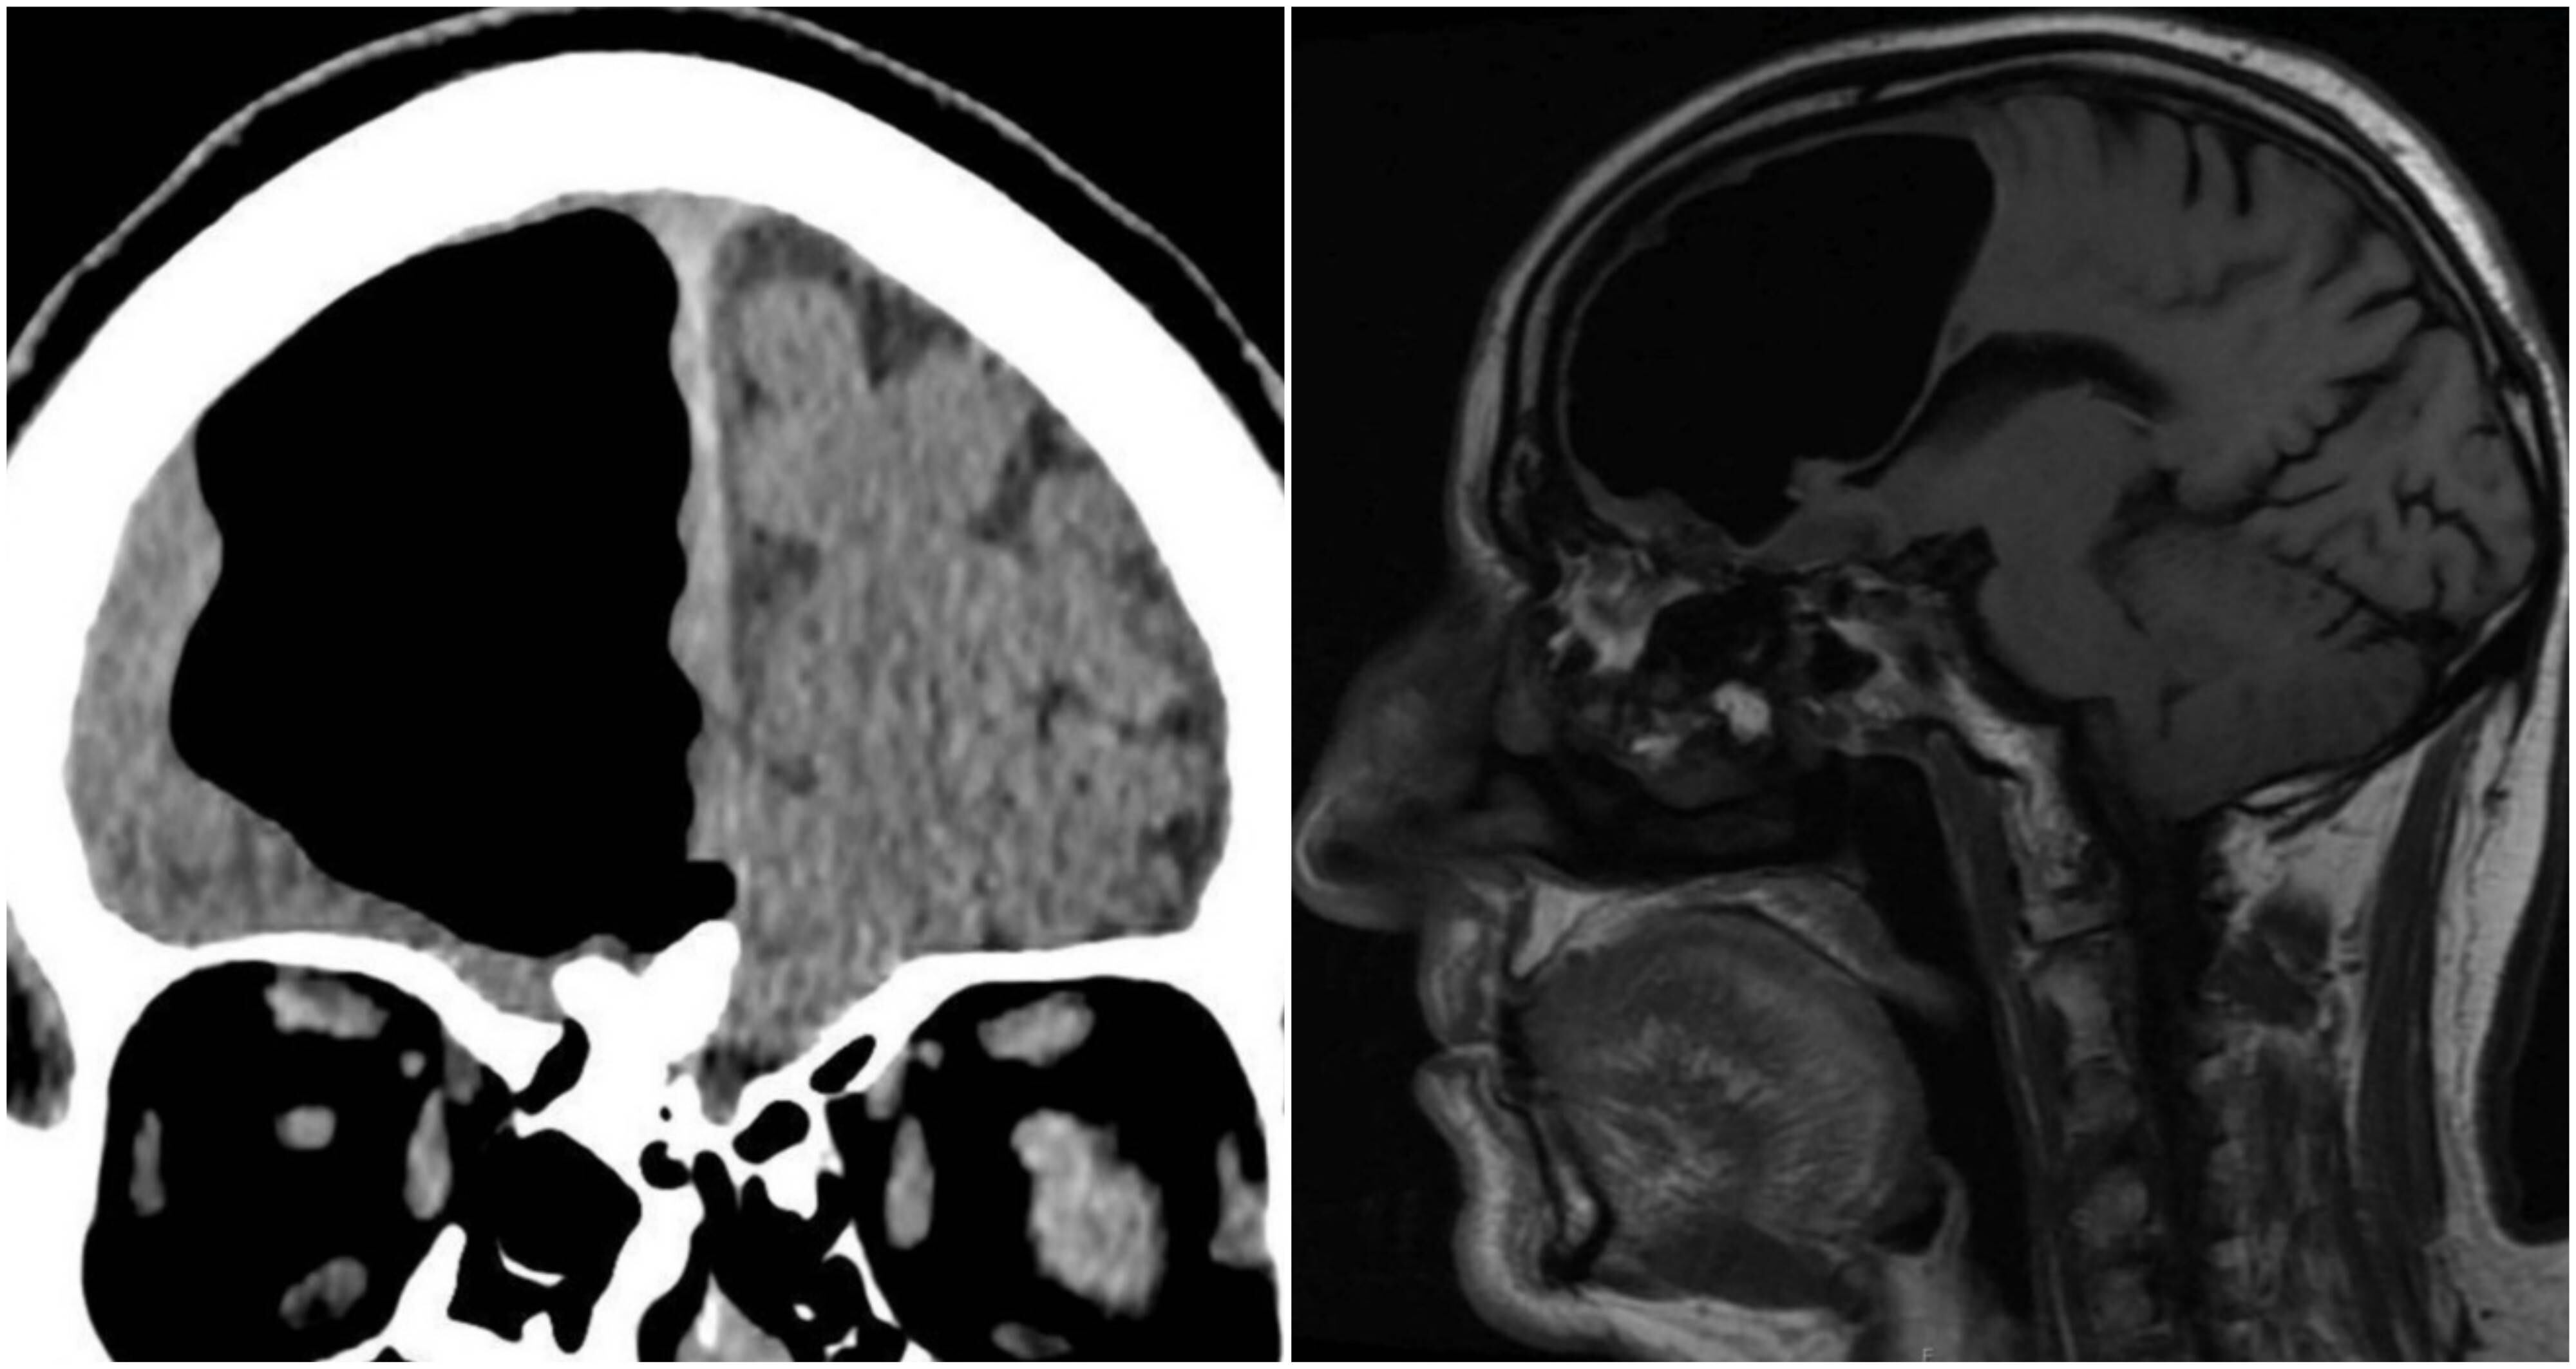

Los doctores no lo podían creer, pero los exámenes eran claros y mostraban una cavidad de aire de unos 9 centímetros en el lóbulo frontal derecho de un hombre de 84 años en el lugar donde debía estar su cerebro.

Tras ello, el hombre fue sometido a una tomografía computarizada y se encontraron con el increíble hallazgo.

Los facultativos creen que la “bolsa de aire” comenzó a desarrollarse luego de un pequeño golpe en la cabeza y que estaba incrementaba su tamaño a medida que el hombre tosía, olfateaba o estornudaba, con lo cual le “inyectaba pequeñas cantidades de aire a la cabeza”.